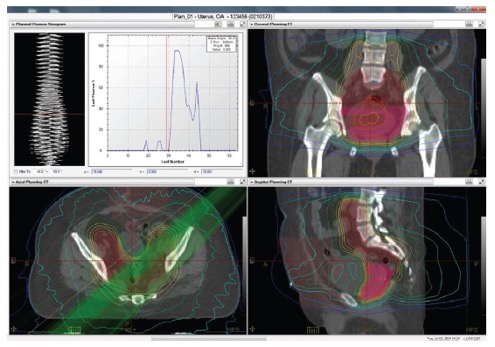

II. Προσαρμοζόμενη ακτινοθεραπεία στο σύστημα TomoTherapy

Το TomoTherapy σε συνεργασία με το σύστημα σχεδιασμού Precision™ και το σύστημα διαχείρισης δεδομένων iDMS™ της εταιρείας Accuray, ενσωματώνουν όλα τα απαραίτητα εργαλεία για την εκτέλεση προσαρμοζόμενων ακτινοθεραπευτικών πρακτικών.

Τα συγκεκριμένα συστήματα περιλαμβάνουν: λογισμικό για τον σχεδιασμό εξαιρετικά σύμμορφων και ομοιογενών δοσιμετρικών κατανομών, ενσωματωμένο αξονικό τομογράφο για καθημερινή λήψη εικόνων αξονικής τομογραφίας του ασθενούς, λογισμικό για την ευθυγράμμιση των καθημερινών εικόνων αξονικής τομογραφίας στις αρχικές εικόνες σχεδιασμού λαμβάνοντας υπόψη τις ανατομικές και βιολογικές μεταβολές του ασθενούς και δοσιμετρικό αλγορίθμο για τον υπολογισμό της δόσης στις καθημερινές εικόνες απεικονιστικής καθοδήγησης.

Οι ανατομικές και βιολογικές μεταβολές του ασθενούς (π.χ., απώλεια βάρους) κατά τη διάρκεια της ακτινοθεραπευτικής αγωγής λαμβάνονται υπόψη με το σύστημα PrecisesART.

Το σύστημα PreciseART δίνει την δυνατότητα στους ακτινοθεραπευτές Ιατρούς να παρακολουθούν την δοσιμετρική ακρίβεια στη χορήγηση της ακτινοθεραπευτική αγωγή και να επιλέγουν πότε απαιτείται αναπροσαρμογή του πλάνου θεραπείας.

Με τον τρόπο αυτό μπορούν να χορηγήσουν θεραπείες με υψηλή ακρίβεια σε κάθε ασθενή.

III. Οι κύριες παράμετροι του συστήματος PreciseART είναι:

I. Χρήση εικόνων MVCT για την ποσοτικοποίηση της επίδρασης των ανατομικών και βιολογικών μεταβολών του ασθενούς

- Αυτόματη σύντηξη των καθημερινών εικόνων αξονικής τομογραφίας με τις αντίστοιχες εικόνες σχεδιασμού της θεραπείας του ασθενούς.

- Ενσωμάτωση στους υπολογισμούς των καθημερινών μετακινήσεων για την ακριβή τοποθέτηση του ασθενούς σε θέση θεραπείας

- Αυτόματος υπολογισμός της χορηγούμενης κατανομής δόσης στον ασθενή με βάση της καθημερινές εικόνες αξονικής τομογραφίας

II. Αυτόματη παρακολούθηση της χορηγούμενης ακτινοθεραπευτικής αγωγής

Το σύστημα περιλαμβάνει εργαλεία που επιτρέπουν στον ακτινοθεραπευτή ιατρό να παρακολουθεί την εκτέλεση της ακτινοθεραπείας και να ενημερώνεται αυτόματα για τις περιπτώσεις εκείνες που απαιτείται αναπροσαρμογή του πλάνου θεραπείας.

- Σύντηξη των παραμέτρων του πλάνου θεραπείας (π.χ., περιγράμματα στόχου και κρίσιμων οργάνων) με τις καθημερινές εικόνες αξονικής τομογραφίας λαμβάνοντας υπόψη τις ανατομικές και βιολογικές μεταβολές του ασθενούς

- Υπολογισμός της καθημερινά χορηγούμενης κατανομής δόσης

- Υπολογισμός της αθροιστικά χορηγούμενης δόσης

- Ενημέρωση της ηλεκτρονικής καρτέλας του ασθενούς για την δοσιμετρική ακρίβεια της χορηγούμενης ακτινοθεραπείας

- Ενημέρωση του ακτινοθεραπευτή ιατρού στην περίπτωση που ο όγκος στόχος ή τα κρίσιμα όργανα λαμβάνουν δόση εκτός των κριτηρίων ανοχής που έχει θεσπίσει.

III. Αξιολόγηση ακτινοθεραπευτικής αγωγής

Το σύστημα διαθέτει εργαλεία για την αξιολόγηση των καθημερινά χορηγούμενων κατανομών δόσης επιτρέποντας στους ιατρούς να αναγνωρίσουν πια πλάνα χρειάζονται αναπροσαρμογή.

- Αξιολόγηση της ευθυγράμμισης του ασθενούς σε θέση θεραπείας.

- Αξιολόγηση των ανατομικών και βιολογικών μεταβολών του ασθενούς κατά τη διάρκεια της ακτινοθεραπευτικής αγωγής

- Αξιολόγηση της καθημερινά χορηγούμενης κατανομής δόσης, της αθροιστικής δόσης μέχρι την συγκεκριμένη συνεδρία καθώς και των δοσιμετρικών διαφορών

- Αξιολόγηση της ανταπόκρισης του ασθενούς στην ακτινοθεραπευτική αγωγή.